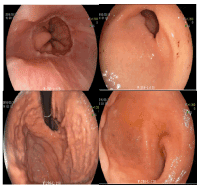

Figure 2. Colon endoscopy: sigmoiditis.